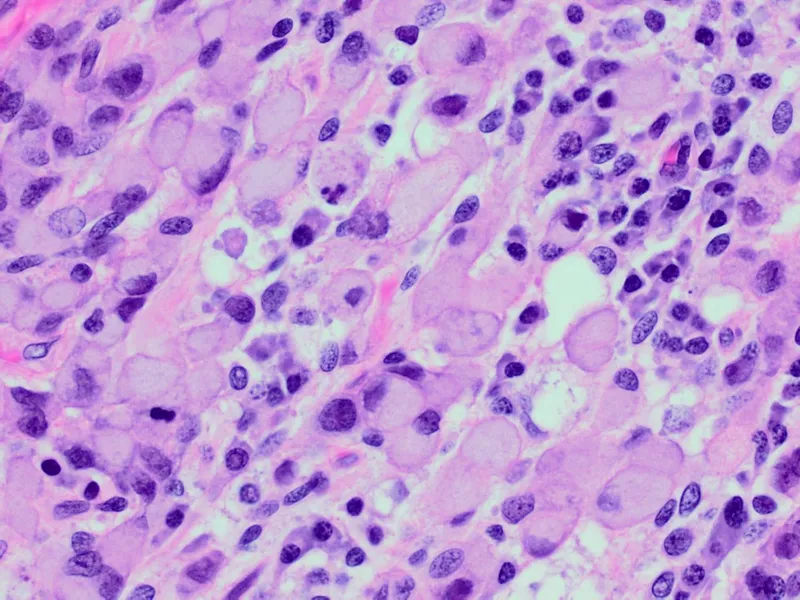

- Diffuse: Signet ring cells; Linitis plastica.

⭐ Diffuse type gastric cancer (signet ring cells, linitis plastica) often presents at an advanced stage and has a poorer prognosis than intestinal type.